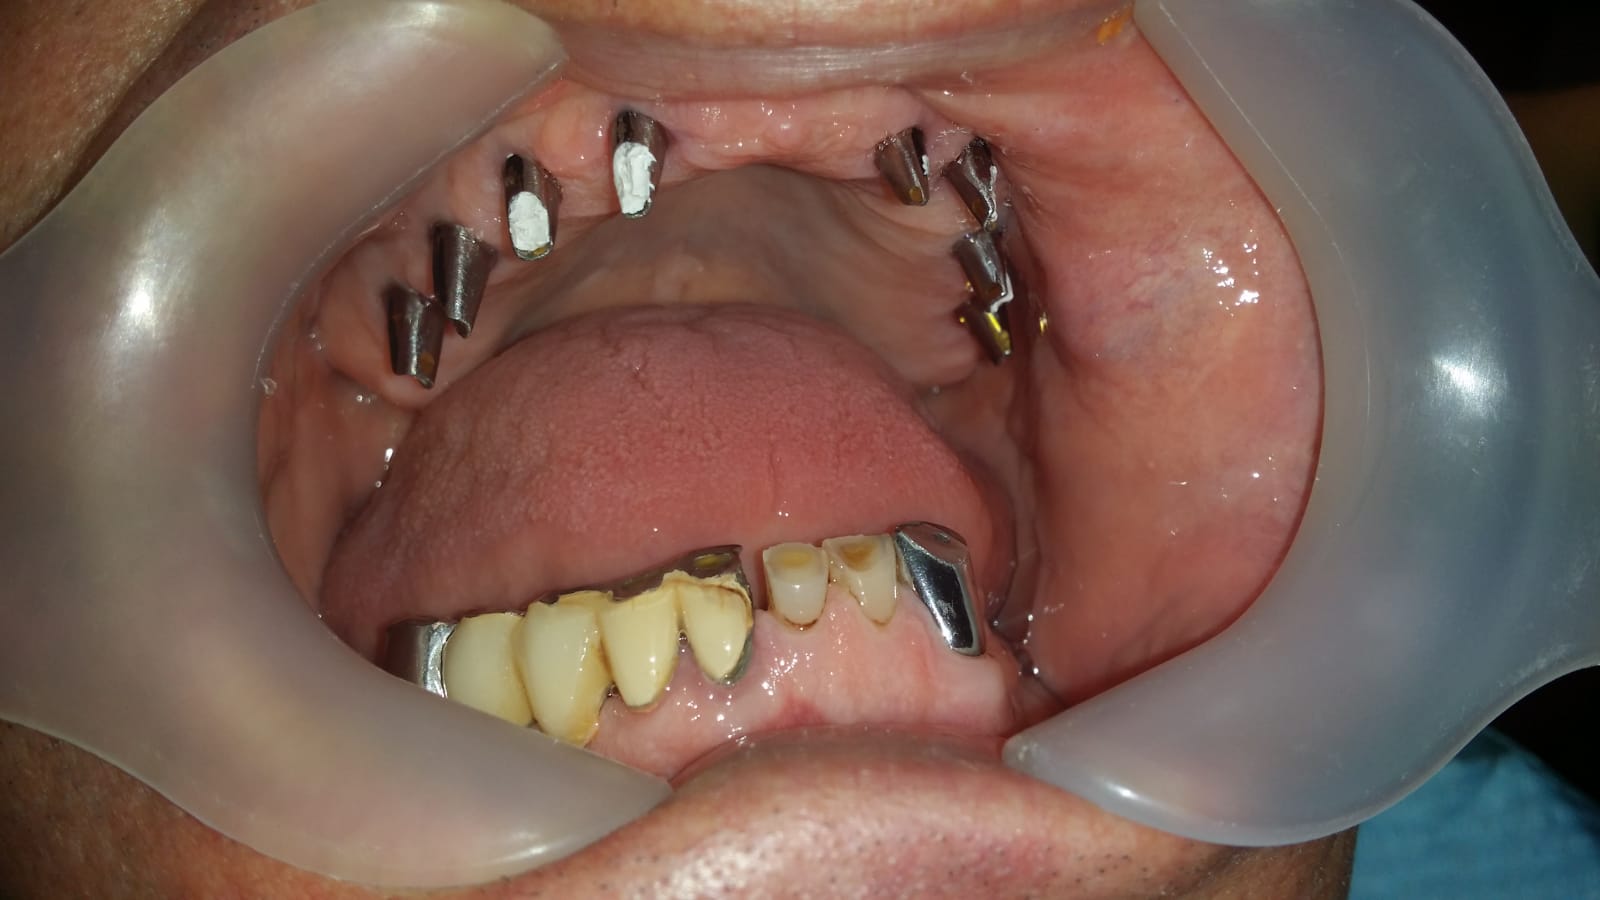

Punte realizată pe 4 implanturi dentare la mandibula și 6 implanturi la maxilar All in One

Punte fixa provizorie realizată la mandibula în 24 ore, pe 4 implanturi dentare